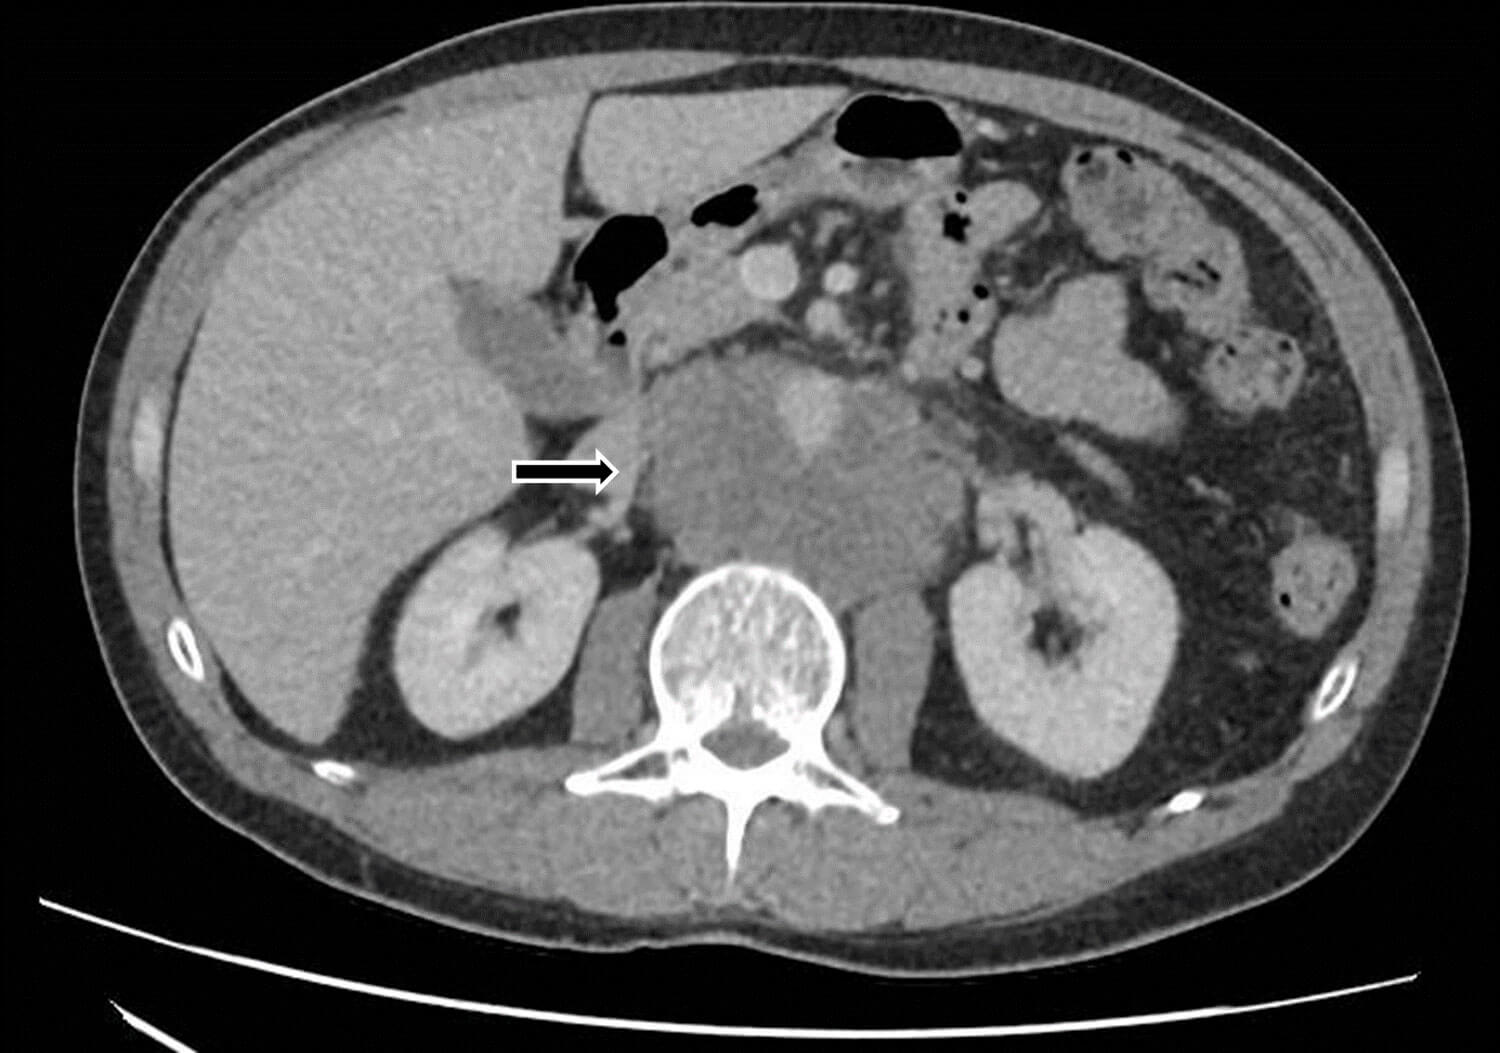

A 43-year-old man attended his GP with a three month history of worsening abdominal and back pain. An ultrasound (US) of the abdomen showed prominent para-aortic lymph nodes and he was referred under the two-week-wait for suspected cancer of unknown primary. A CT abdomen and pelvis demonstrated a large conglomerate retroperitoneal mass, suspicious for lymphoma, as well as a large pulmonary embolus (Figure 1).

Figure 1: Large retroperitoneal mass extending to the common iliac vessels.

The patient was commenced on low molecular weight heparin and a CT-guided biopsy was performed - histology showed metastatic seminoma, and he was referred to the urology team. A subsequent US testes showed a 1.5cm right sided testicular lesion (Figure 2).